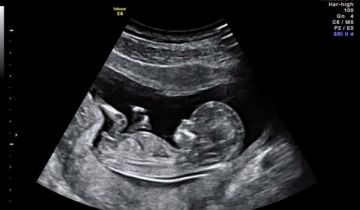

Tại sao siêu âm không thấy tim thai ?

Tim thai là một dấu hiệu quan trọng để đánh giá tình trạng phát triển và sức khỏe của tha nhi. Tim thai thông thường sẽ ...

Nguyên nhân dẫn đến không có tim thai.

Có thể tính tuổi thai bằng máy siêu âm?

Hiện nay, phương pháp chính xác nhất để tính tuổi thai là bằng máy siêu âm. Phương pháp này cho độ chính xác cao do dựa ...